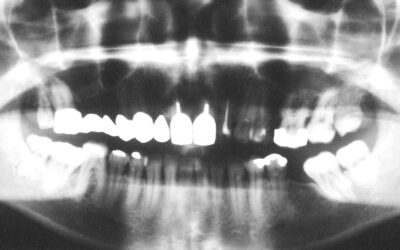

Am besten lernt man aus eigenen Fehlern und dadurch, dass man die Gründe des Scheiterns analysiert. Schlecht ist es, wenn man jeden Fehler erst selbst machen muss um zu lernen. Viel geschickter ist es, aus den Fehlern anderer zu lernen. OPG aus 1989 zur Kontrolle der...